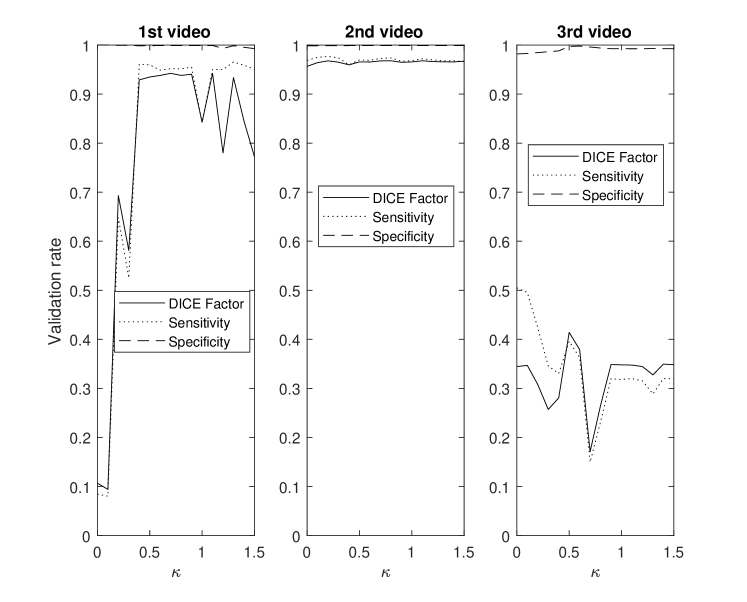

This section demonstrates the robustness of the algorithm for each parameter along with the relative importance of each parameter on the overall performance. This enables the identification and potential removal of weak features from the energy function in order to improve computational efficiency. For this study, the average DICE factor, sensitivity, and specificity of three different clips versus the initial parameters , , , , and are shown in Figs. 5-10. In the all of these figures, one can easily see that the specificity is always very close to one indicating a relatively small rate of .

Fig. 8 highlights that different videos demonstrate considerable variance in sensitivities versus . Sensitivity was relatively stable for ranging between 0.4 and 0.9, hence was set to 0.8.